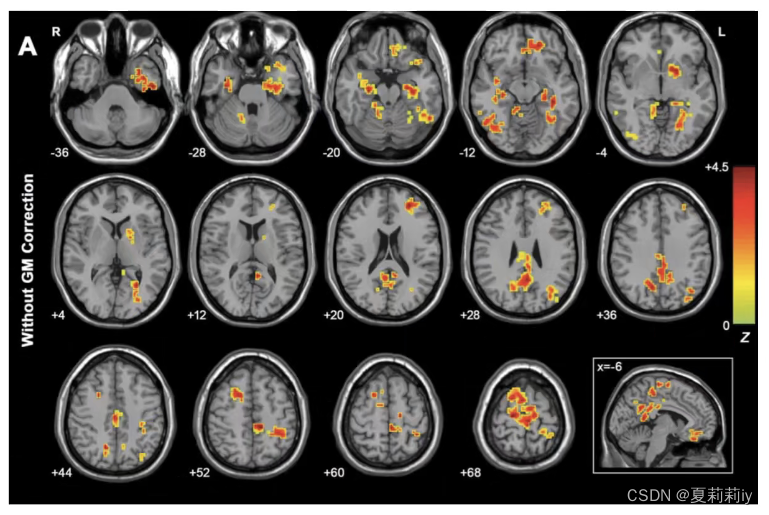

(4)Two-Sample T-Test

①One Sample是没有实际意义的,一般要使用Two-Sample来进行数据分析

②在左方添加两个文件夹(值第一组减去第二组的值,所以顺序很有关系)

③上图中Covariate Images添加的灰质密度图像,Covariate Images为图像协变量

④功能上一般是3*3*3的voxel size,但结构上一般是1*1*1或1.5*1.5*1.5。此时用Utilities→Image Reslicer可以将结构像变成功能像的大小,否则在这不一样大会报错

⑤上图中Text Covariates添加了头动,Text Covariates是文本协变量